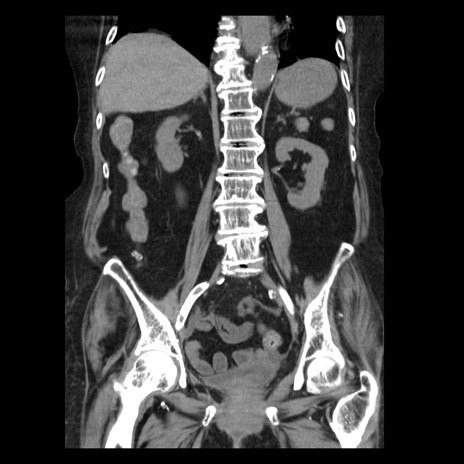

症例14(冠状断像)

【症例】 90歳代女性

【主訴】 腹痛・嘔吐

【現病歴】今朝から左側腹部痛を認めた。 経過観察していたが、嘔吐を認めたため来院。

【既往歴】 子宮癌術後

【身体所見】 意識清明、BP 127/54mmHg、P 98bpm Sp02 95%(RA)、BT 35.8°C、腹部平坦・軟腸ぜん動音聴取良好、右下腹部圧痛(+) 反跳痛なし

【データ】WBC 9800、CRP 0.46